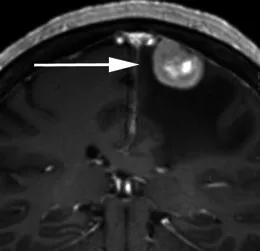

案例六:70岁头痛女性患者。增强冠状位T1加权序列显示右中央前回受压(箭头),病灶轻度不均匀强化,宽基硬脑膜附着,周围显著血管源性水肿。T2加权序列呈高信号(与灰质对比)。术后病理证实为原发性乳腺癌腺癌转移。

案例七:63岁男性患者,滤泡性淋巴瘤病史。增强冠状位T1加权序列显示右中颅窝轴外占位,宽基硬脑膜附着伴硬脑膜增厚,并向轴内延伸至右颞叶。硬膜成分均匀强化,轴内成分轻度不均匀强化,周围水肿及占位效应明显。影像表现类似伴轴内侵犯的脑膜瘤,但病理确诊为淋巴瘤。